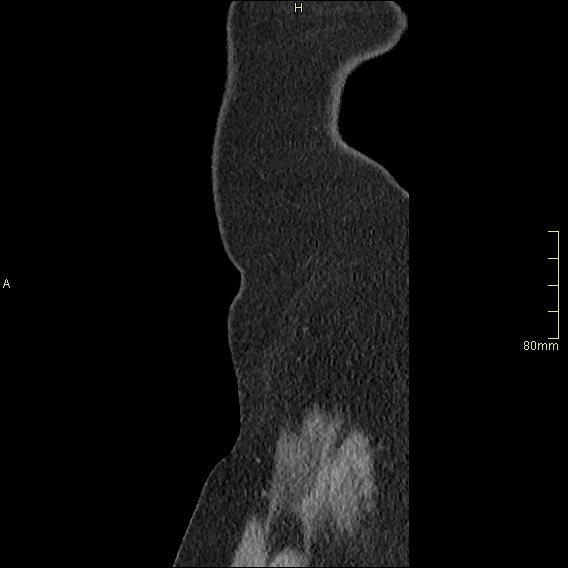

For patients over the age of 40, a non contrast KUB, and seperate nephrogenic and excretory (delayed) phases will be performed. For all patients under the age of 40, a non contrast KUB and a COMBINED dual nephrogenic/excretory phase will be performed. Image examples of this can be seen below.

Over 40 Years of Age

CT Urogram- Nephrogenic Phase (Axial)

CT Urogram- Excretory Phase (Axial)

CT Urogram- Nephrogenic Phase (Coronal)

CT Urogram- Excretory Phase (Coronal)

CT Urogram- Nephrogenic Phase (Sagittal)

CT Urogram- Excretory Phase (Sagittal)